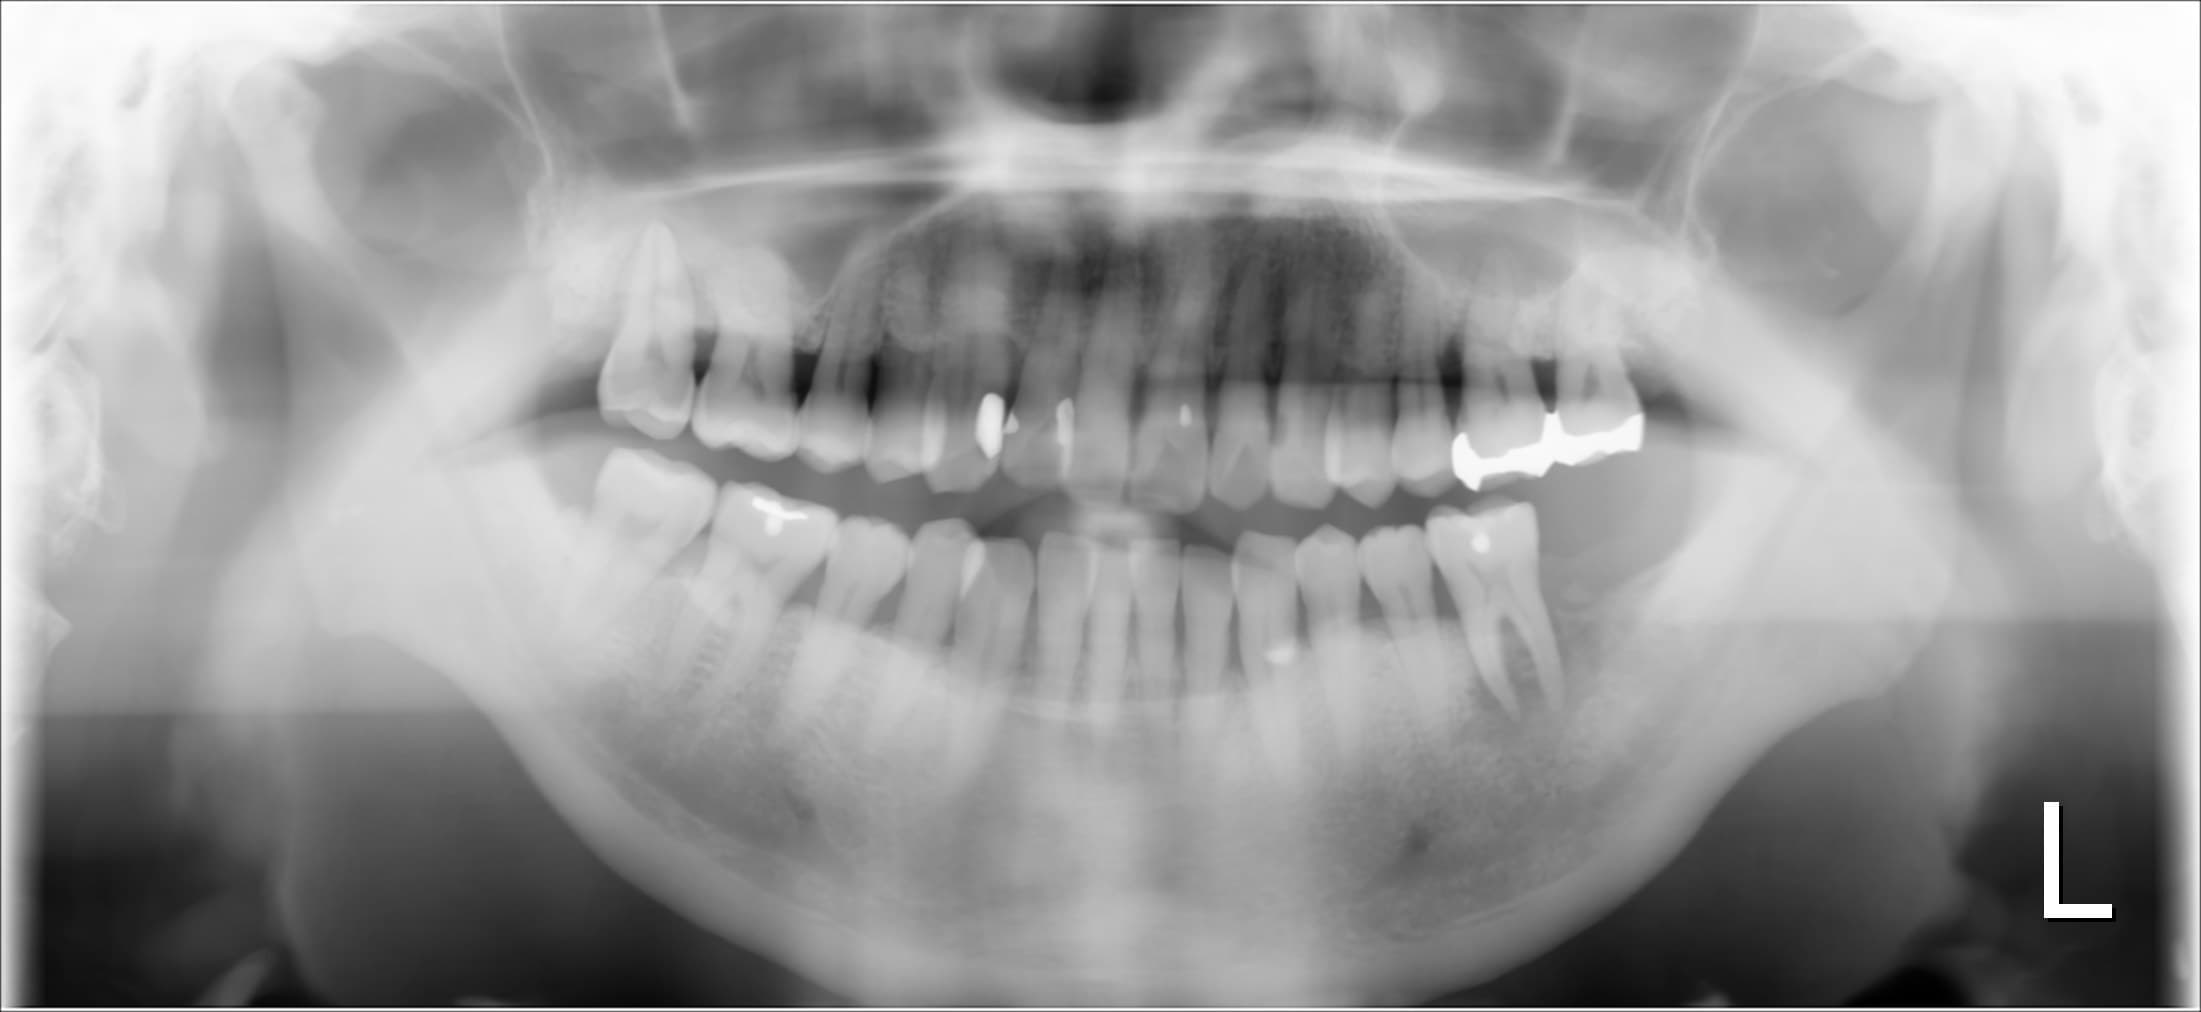

こんにちは。 南館歯科クリニックの歯科衛生士の山崎です。 今回ご紹介する歯周病専門治療のケースは、左下奥歯の急な激しい痛みで来院された60代男性の方です。 去年の2月に脳腫瘍摘出の手術を…